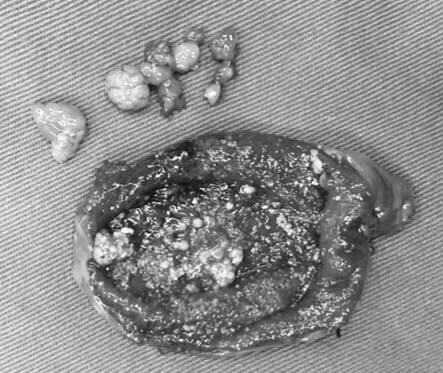

· 胆囊上长"肉肉",怎么办? ( ) 张先生, 34岁,近来一直感觉右上腹不适,经b超检查提示胆囊息肉样病变,已有1厘米大小,于是在医生的建议下做了胆囊切除术。术后,切除的胆囊病理检查报告提示慢性胆囊炎伴腺肌瘤样增生。 张先生的胆囊到底怎么了? 首先,我们说说胆囊息肉样0805 胆囊多发息肉怎么办呢? 0702 多发性胆囊息肉怎么办? 948; · 长了胆囊息肉怎么办? 近年来,人们在进行常规健康体检时,越来越多地被检查出胆囊"异常"——胆囊息肉。 胆囊上长出来的小息肉虽对日常生活不会有太大影响,但却让不少患者心理蒙上了一层"癌变"的阴影。 在临床上,针对"胆囊息肉"的治疗分为两种,一种只需观察治疗,定期复查即可,另一种则建议尽早手术切除,以防癌变。 那么,长了胆囊息肉

胆囊息肉怎么办- · 胆囊息肉、胆囊结石严重吗? 胆囊息肉指胆囊内生长出来的息肉样的病变,其中大多数小于10cm的胆囊息肉是良性的疾病,恶变的几率较低,不必过分忧虑,只需要定期复查即可。 但是大于10cm以上的则有癌变的可能,此时就需要提高警惕必要时手术治疗,以避免贻误病情。 胆囊结石是胆道系统最常见的一类疾病,结石本身对身体没有影响,但其可能引起胆囊炎 · 胆囊上长"肉肉",怎么办? 21 04/17 分享 评论 复旦大学附属华山医院 aa 张先生,34岁,近来一直感觉右上腹不适,经b超检查提示胆囊息肉样病变,已有1厘米大小,于是在医生的建议下做了胆囊切除术。术后,切除的胆囊病理检查报告提示慢性胆囊炎伴腺肌瘤样增生。 张先生的胆囊到底怎么